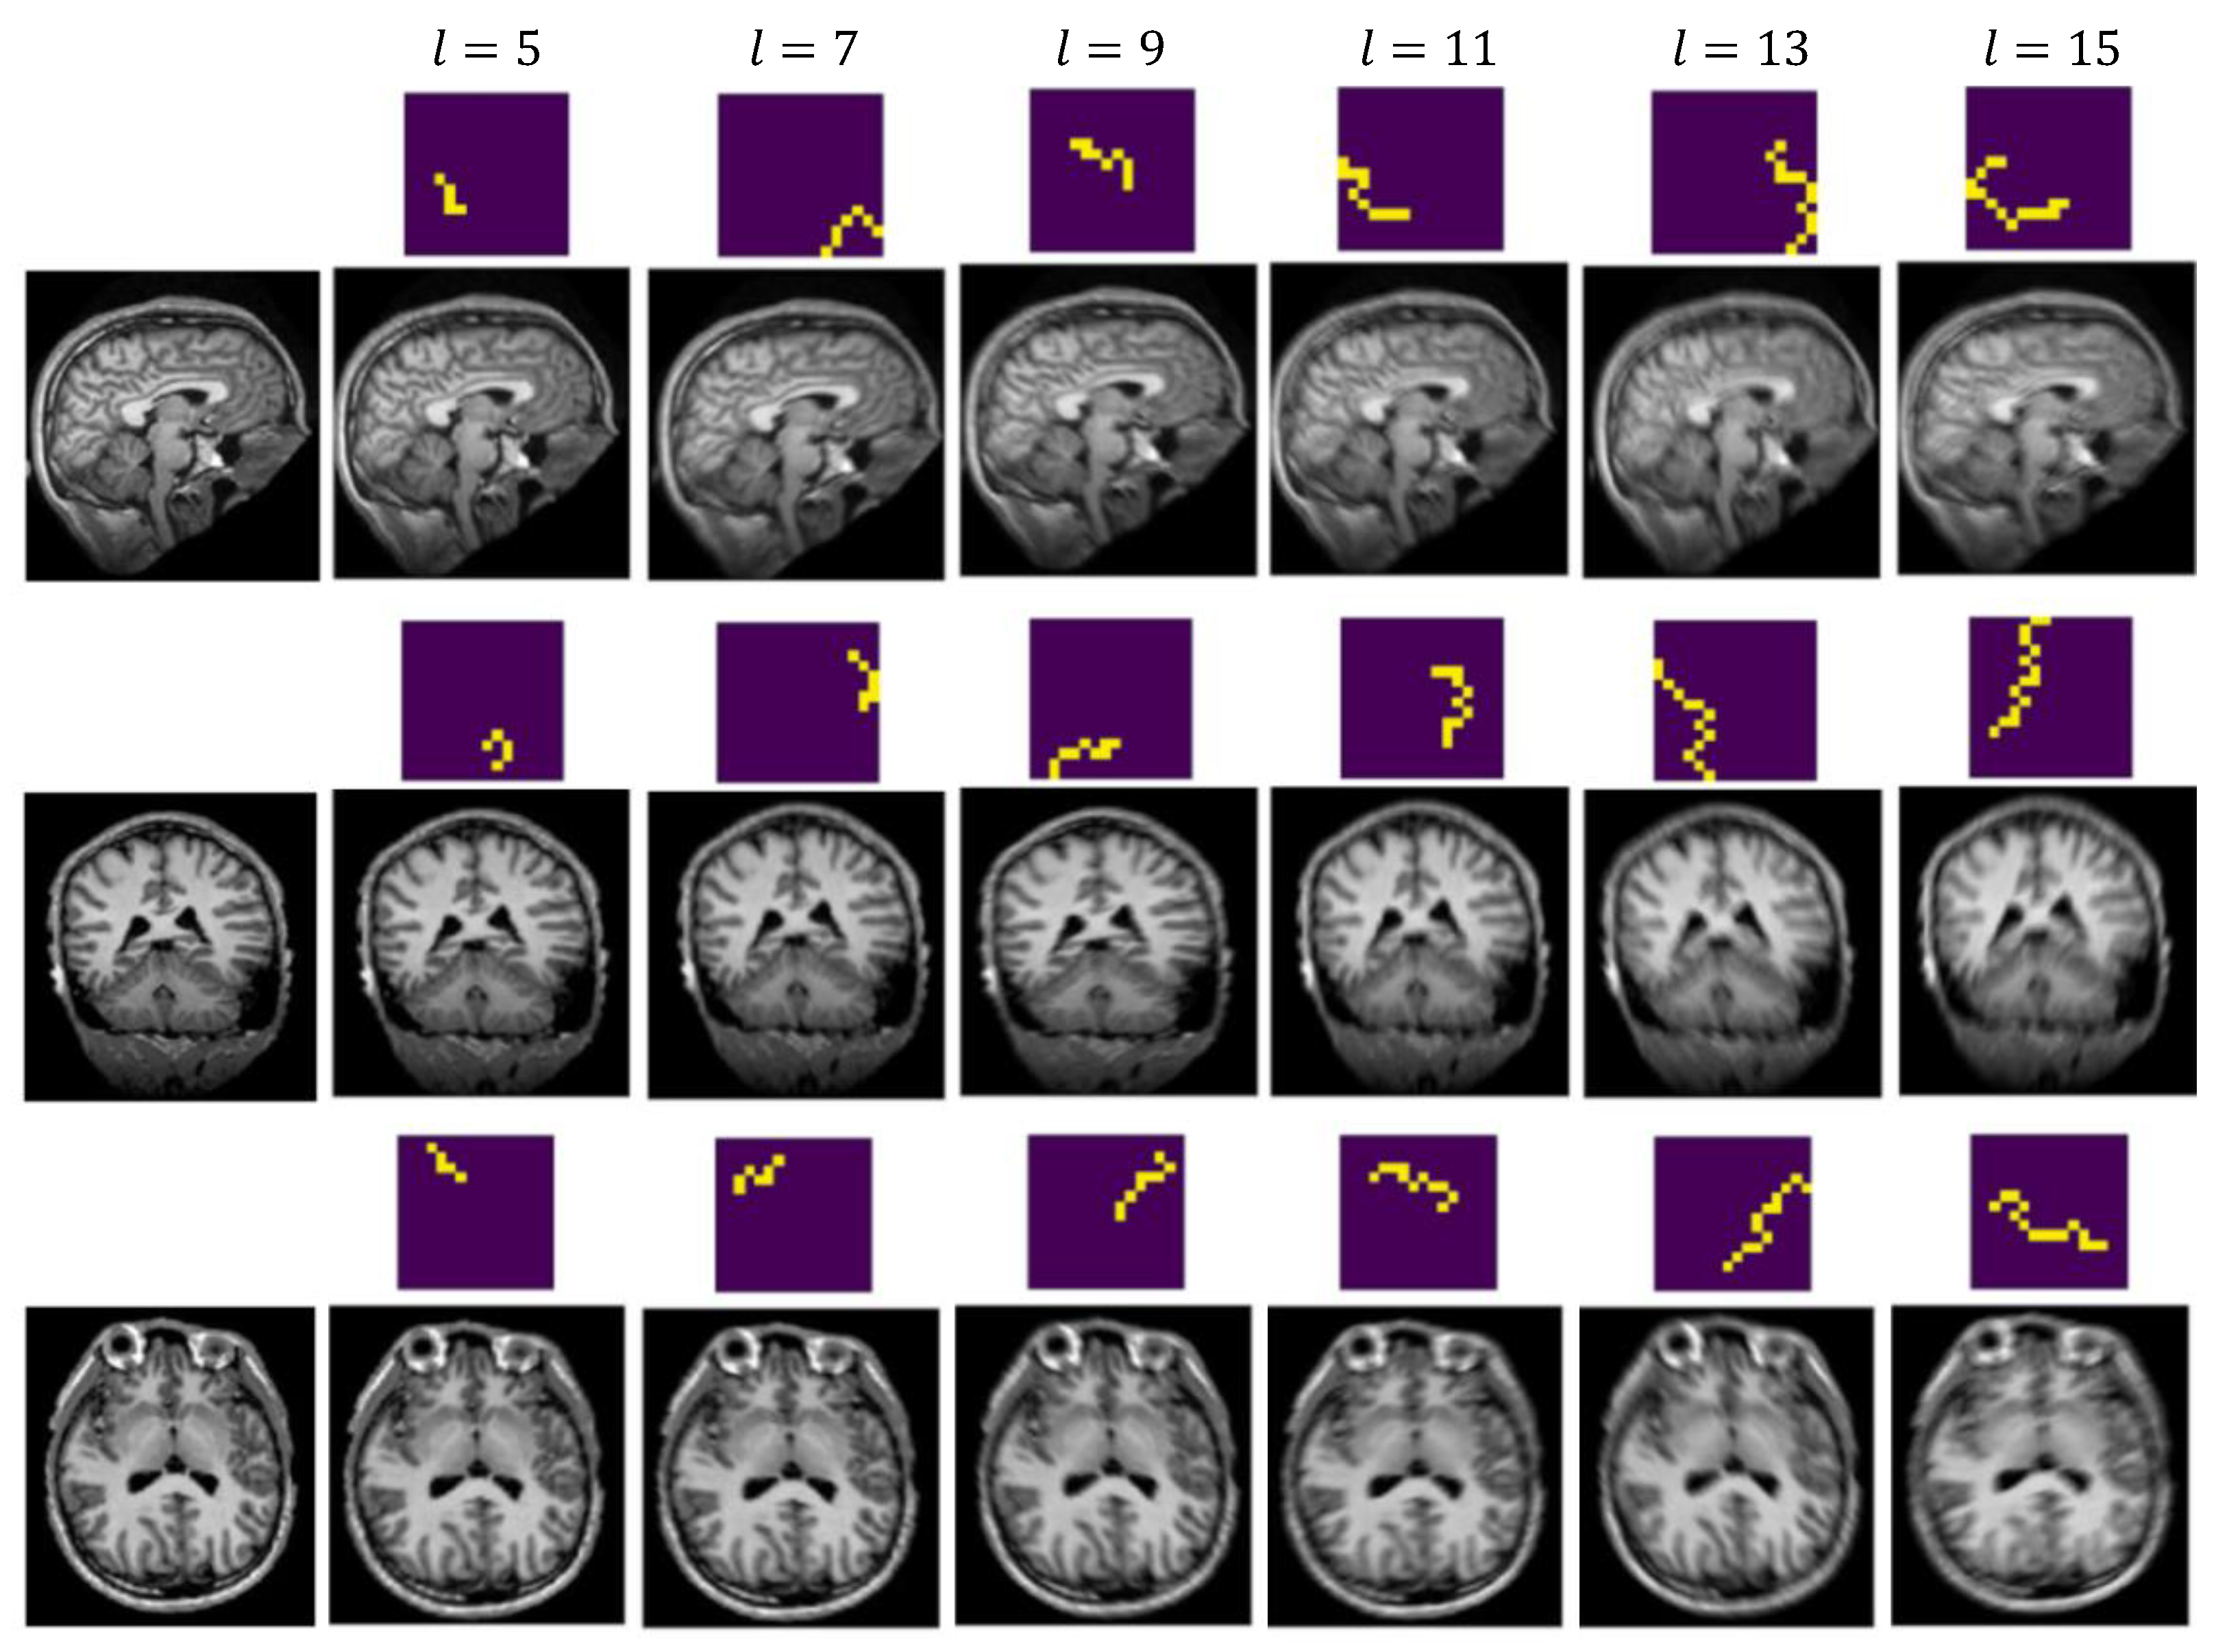

4.2. Synthetic Datasets

4.2.2. Generate Synthetic Artifact-Affected Data